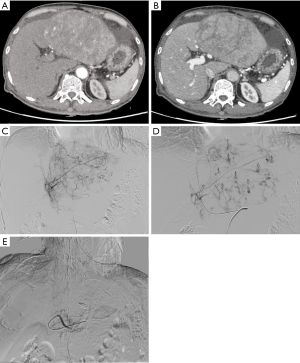

All the 92 HCC patients were treatment-naïve, and DEB-TACE was applied in the first interventional therapy. The success rate was 98.9%. Among them, 43 patients had a single nodule while 49 (64%) had multiple nodules. A total of 179 nodules were found, among which 33 VLs (18.4%) (15 stable VLs and 18 unstable VLs) were detected. For unstable VLs, embolic agents were used for subsequent embolization sessions until both VL and tumor-feeding vessels disappeared. In one patient with unstable VL, the diameter of the lesion was 3.0 cm. Embolization using DEBs continued until SACE level IV was achieved. Abdominal distension and decreased blood pressure occurred 6 hours later. The uncoagulated blood was extracted by diagnostic abdominal puncture. The clinical diagnosis was hemorrhage due to hepatic rupture. A second angiography revealed that the hepatic artery and its branches remarkably contracted and thus the superselective catheterization could not be completed. The main hepatic artery was embolized with gelatin sponge. The patient died of abdominal hemorrhage and multiple organ failure 48 hours after the operation. In the VL group, 2 patients (2 nodules) with stable VL were found to have residual lesions near the VLs. After CT-guided radio frequency ablation (RFA), the residual lesions disappeared (Figure 2). The nodules evaluated as CR were followed up regularly and the remaining nodules were treated with a second DEB-TACE or CT-guided RFA.

During the follow-up, two stable VLs were found to have residual tumors in the VL region, along with obvious necrosis in other regions. CT-guided local ablation was then applied. The possible etiology might be as follows: the extravascular shunt of DEBs leads to incomplete embolization of tumor-feeding vessels, resulting in incomplete tumor necrosis. In one patient with one unstable VL, embolization using DEBs alone was applied because the lesion was small. It might because the microspheres re-distributed along with blood stream over time and then re-located, leading to incomplete embolization; VL gradually grew with the increased intratumoral blood pressure and finally became ruptured. Neither case has been reported in the literature.